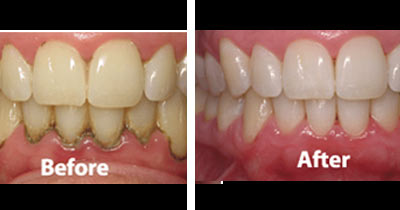

Dr. PRASHANTHY.R.BDS, MDS, FICOI,DICOIPeriodontist / Implantologist-Board certified Diplomate (ICOI )Healthy Gums and Teeth for a Beautiful Smile

Specialist inPeriodontist